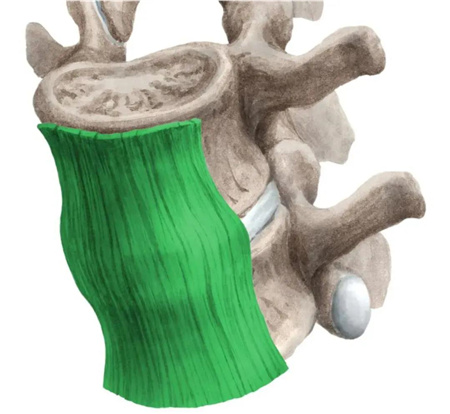

颈椎病是由于颈椎间盘退行性变、颈椎骨质增生所致颈椎管或椎间孔变形、狭窄,刺激、压迫颈部脊髓、神经根、交感神经及软组织造成其结构或功能性损害所引起的一系列临床症状的综合征。颈椎病可分为颈型、神经根型、脊髓型、椎动脉型、交感神经型和其他型。颈椎病临床常表现为颈、肩臂、肩胛上背及胸前区疼痛,臂手麻木,肌肉萎缩,甚至四肢瘫痪,以及神经压迫导致的失眠、头痛、头晕等。可发生于任何年龄,以40岁以上的中老年人为多。颈椎病具有发病率高,治疗时间长,治疗后极易复发等特点。

(2)暴力导致纤维环损伤,出现薄弱环节,为颈椎间盘突出打下基础。

(3)前纵韧带撕裂造成颈椎不稳,日后逐渐加重,出现椎体后缘骨质增生,可加速受损节段。